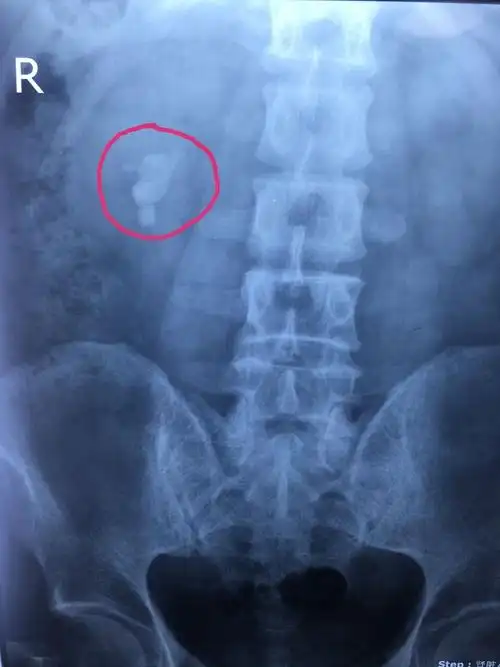

肾结石x光片

5月26日,结石距离膀胱一步之遥;这位输尿管结石患者,因结石梗阻后,肾

8公分大的肾结石,医生也惊呆了!